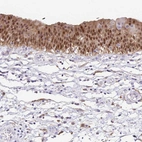

Immunohistochemistry analysis in human stomach and tonsil tissues using HPA005469 antibody. Corresponding ANXA10 RNA-seq data are presented for the same tissues.